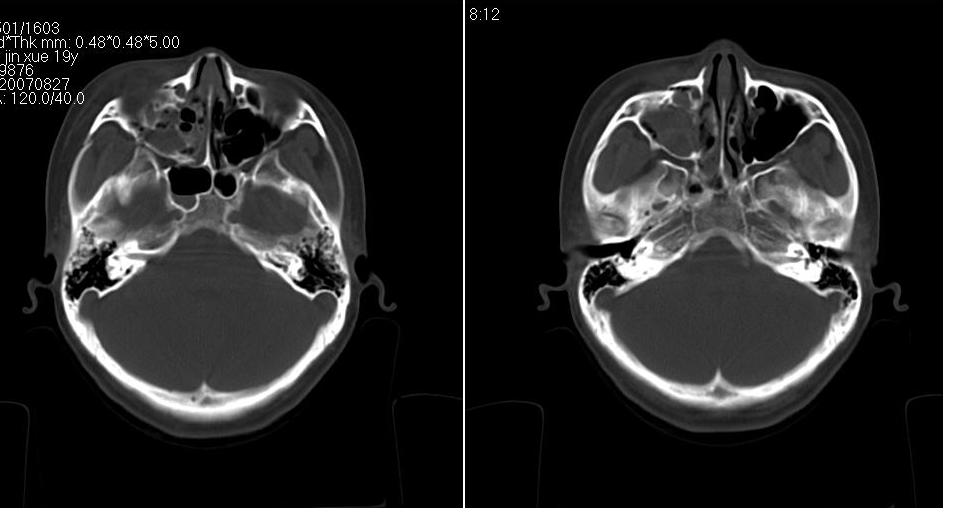

标题: CT9542:鼻窦CT平扫 [打印本页]

标题: CT9542:鼻窦CT平扫

女 18岁,外伤.

右侧上颌窦前壁骨折,窦腔积液.

右侧上颌窦前后壁及右颧骨弓骨折,窦腔积液。

右侧上颌窦前壁、外侧壁骨折,内侧壁可疑骨折,窦腔积液

右侧上颌窦前后壁骨质均不连续,窦腔内见一致性高密度影,右睑部软组织肿胀

1,右上颌窦前后壁骨折,伴窦腔积血可能性大

2,右睑部软组织肿胀

右侧上颌窦前壁、外侧壁、内侧壁骨折,伴窦腔积液;右侧颧弓骨折。

1 、 右侧上颌窦前壁、外侧壁、内侧壁骨折并窦腔积液(血);右侧上颌窦前壁骨折累及同侧鼻泪管;

2、右侧颧骨骨折。

右侧上颌窦前后壁及颧弓骨质均不连续,窦腔内见一致性高密度影,右面部及眼睑部软组织肿胀

1,右上颌窦前后壁骨折伴窦腔积血,右侧颧弓骨折.

2,右面部及眼睑部软组织肿胀